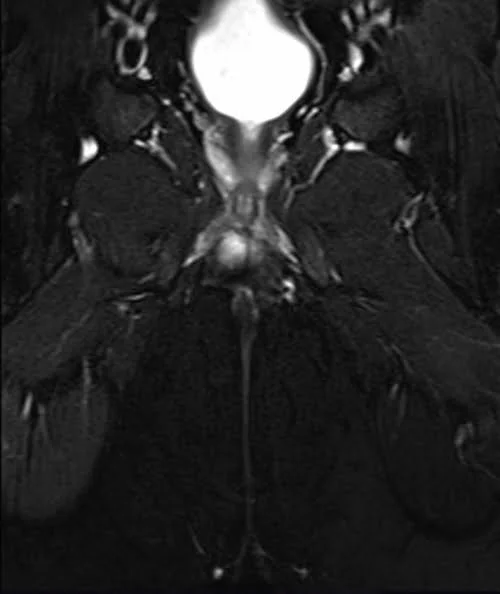

LUMBOSACRAL PLEXUS